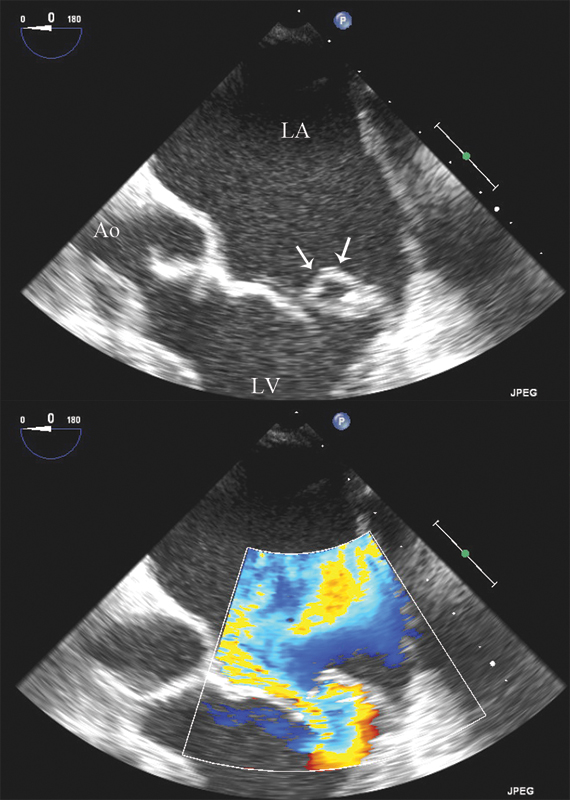

فحوصات تشخيصية لبعض امراض القلب والشرايين التاجية